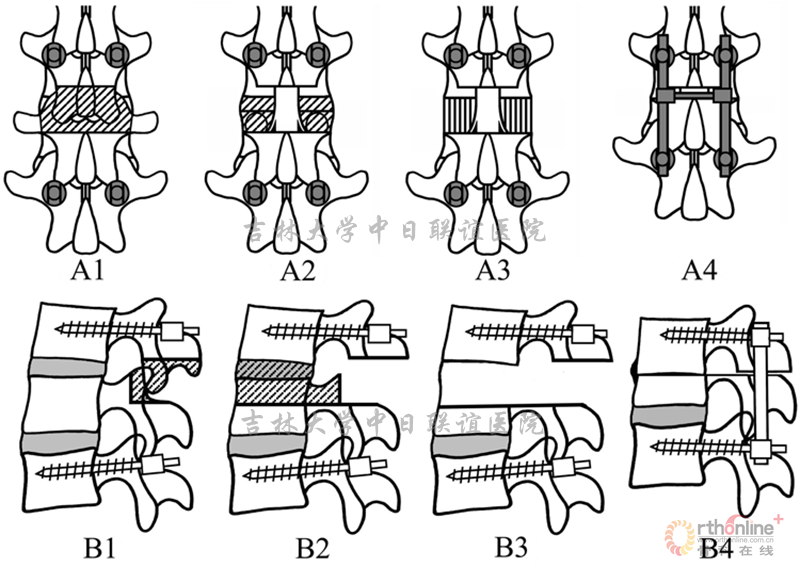

A1.B1:T12/L2植入椎弓根螺钉后,切除T12下1/2及L1上1/3椎板及T12/L1关节突;

A2.B2:磨钻磨除L1上3/4椎弓根,并经磨除的椎弓根磨除L1椎体上部分,然后切除T12/L1间盘及后纵韧带;

A3.B3:截完后的脊柱形态。截骨线应平行于L1下终板和T12上终板;

A4.B4:截完后的空间通过T12/L2钉棒系统逐渐加压闭合。